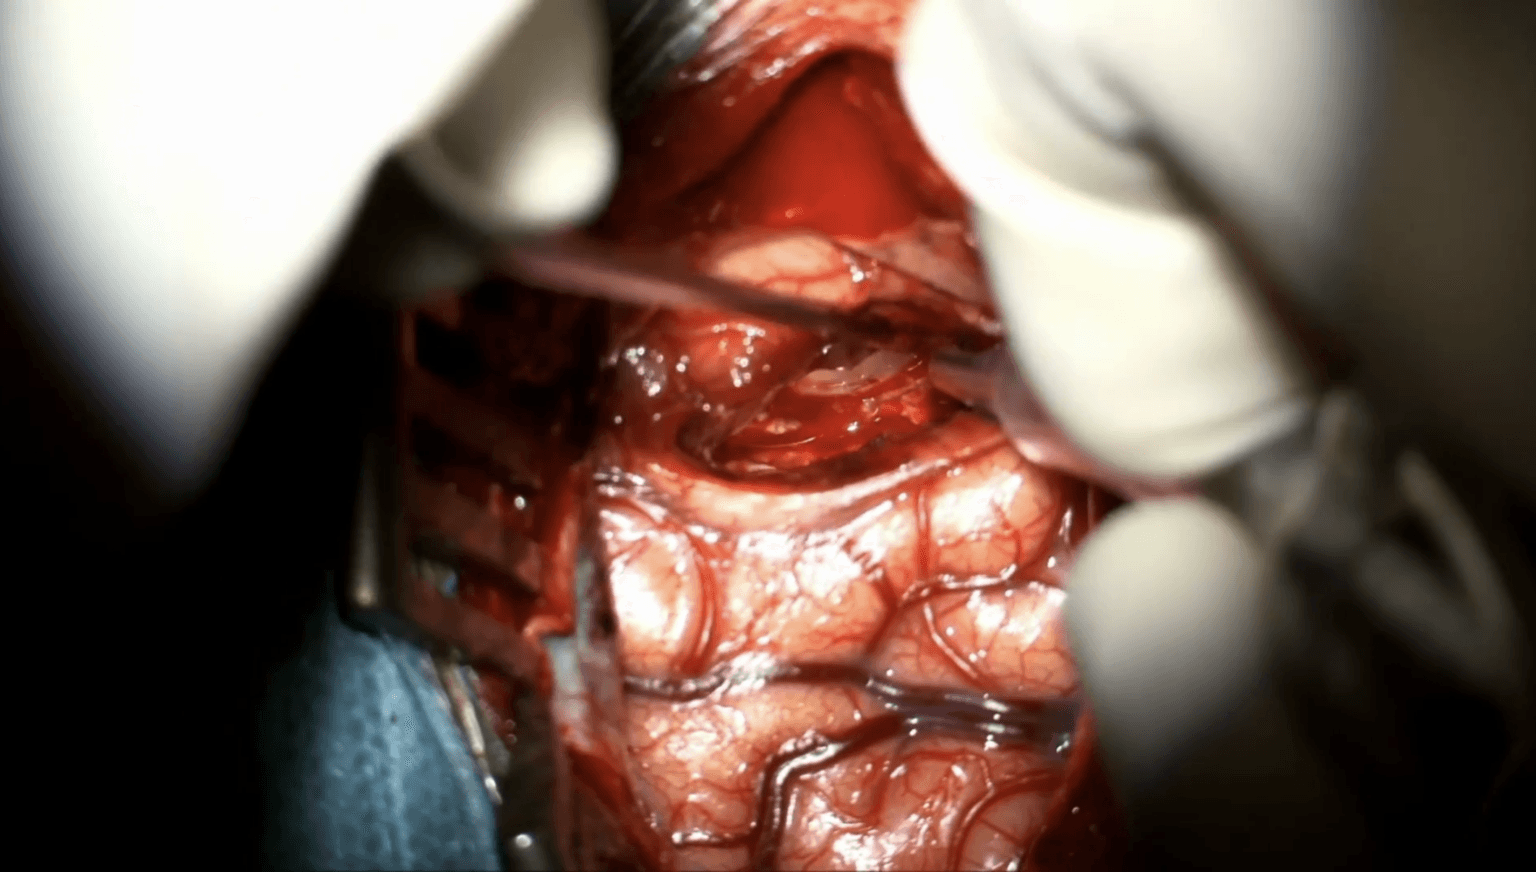

Resección de schwannoma vestibular Koos III guiada con fluoresceína

El prof. Mastronardi realiza la resección microquirúrgica de un schwannoma vestibular Koos III guiada con fluoresceína mediante abordaje retrosigmoideo.